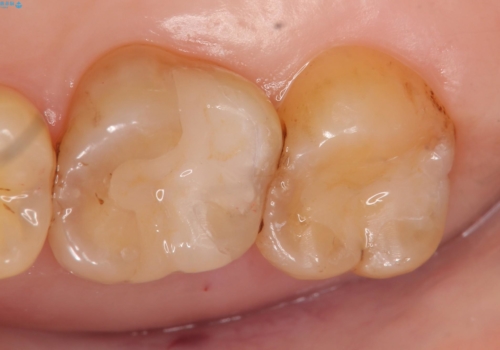

銀歯及び虫歯を除去後、セラミックインレーによる修復を行いました。

- セラミックインレー…¥70,000×2費用は治療当時の料金となります

当院のセラミックインレーはemaxという強度と審美性に優れた材料を使用しています。

またプレス方式でインレーを製作しているため、削り出しで製作するCADCAMより優れた適合性も持ち合わせており、虫歯が再発しにくい修復物です。